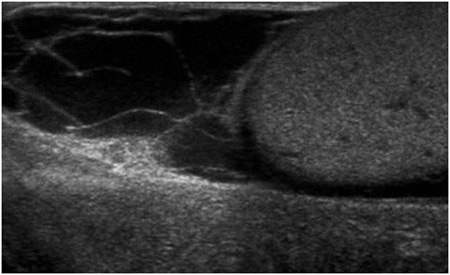

Ábra. Ultrahangos képalkotó hydrocele.